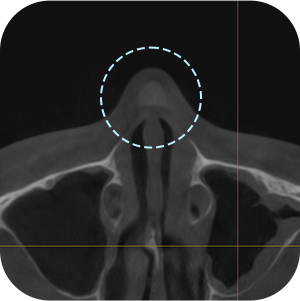

The implant information from the previous surgery is checked

Functional problems such as a deviated septum are checked for

The current implant location is checked

Nasal CT scan, is it necessary?

ASince this is a revision surgery,

a more precise diagnosis is a must!

external appearance and internal functional

problems of the nose are accurately

diagnosed through 3D-CT.